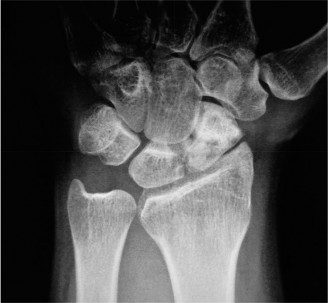

For the second patient, standard PA radiographs immediately reveal the diagnosis. We observe the classic Terry Thomas sign—a widening of the scapholunate interval greater than 3 mm. Furthermore, the lateral radiograph demonstrates a Dorsal Intercalated Segment Instability (DISI) deformity, characterized by a radiolunate angle greater than 15 degrees (lunate extended) and a scapholunate angle greater than 60 degrees.

Advanced imaging, particularly Computed Tomography (CT), is highly beneficial for preoperative templating. A fine-cut CT scan accurately maps the extent of the degenerative changes. In scapholunate advanced collapse (SLAC), arthritis follows a highly predictable, sequential pattern. It begins at the radial styloid-scaphoid articulation (Stage I), progresses to involve the entire radioscaphoid fossa (Stage II), and eventually encompasses the capitolunate joint as the capitate migrates proximally into the widened SL gap (Stage III). Notably, the radiolunate joint is universally spared in SLAC wrist due to the concentric, congruent nature of the lunate fossa and the preservation of the short radiolunate ligaments.